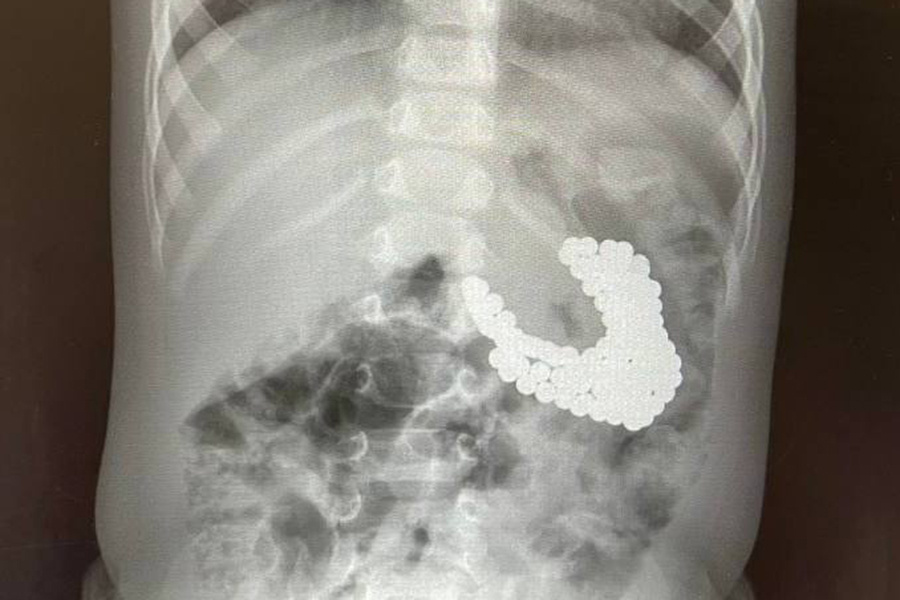

Врачи Центра Леонида Рошаля спасли полуторагодовалого мальчика, проглотившего 130 магнитов и литиевую батарейку. Об этом сообщает пресс-служба минздрава Московской области.

Мальчик поступил в Детский клинический центр им. Л.М. Рошаля с подозрением на проглатывание инородных тел. В ходе обследования в желудке ребенка врачи нашли скопление магнитов и батарейку.

«Магниты сцепились друг с другом, что привело к повреждению слизистой оболочки и образованию язвы. Действовать нужно было быстро. <...> Ребенок глотал магниты в разное время, поэтому некоторые из них уже переместились в кишечник», — рассказал заведующий эндоскопическим отделением Александр Иноземцев.

Металлические шарики достали с помощью специальных инструментов в ходе гастроскопии. Некоторые из них можно было извлечь только хирургическим путем, через маленькие разрезы в брюшной стенке.